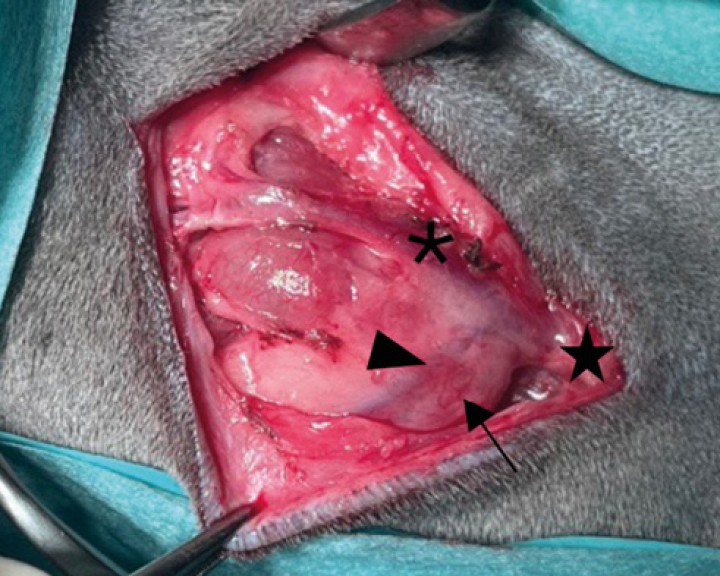

Disección de tejido subcutáneo sobre la glándula salivar. Puede observarse la ramificación de la vena yugular externa en la rama maxilar ( * ) y la rama linguofacial (<); entre ambas ramas se aprecia la glándula salivar mandibular cubierta por su cápsula. Podemos ayudarnos con retractores de Senn Miller para la exposición y fácil disección de los tejidos.

Disección roma de las ramas maxilar ( * ) y linguofacial ( > ) por el aspecto lateral de la glándula mandibular y de la vena yugular externa (estrella) en el aspecto caudal de dicha glándula y linfonodos mandibular (flecha) y retrofaríngeo medial. Ante la sospecha de neoplasia de glándula salivar se realiza excisión del linfonodo para estadiaje.